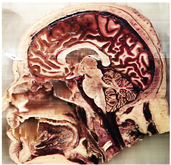

Table 2, Table 3, Table 4 and Table 5 present the results obtained through the multi-objective optimization image enhancement approach. Specifically, Table 2 and Table 3 show the results for natural images, while Table 4 and Table 5 display medical images. The tables are organized as follows: the first and second columns list the image names and their corresponding original, unenhanced versions. The third to fifth columns showcase the selected points from the Pareto front, representing the maximum contrast, knee point, and maximum detail, in that order. The final column illustrates the obtained Pareto front through the optimization process, with red, green, and orange points indicating the images that achieved maximum contrast, knee point, and maximum detail, respectively.

Table 4.

Medical image results—1.

As observed in the results, the images extracted from the Pareto front significantly maximize contrast and detail compared to the original images. In all study cases, the original image is dominated by the solutions extracted from the fronts, demonstrating the approach’s effectiveness in improving visual quality. However, the differences among the three enhanced images for each problem require a more detailed analysis.

For medical images, there are instances where differences are more perceptible. For example, in the Medical3 image, the maximum contrast solution makes it difficult to visualize the internal details of the basophil (a white blood cell highlighted in the box), which could result in a less accurate interpretation. In contrast, the knee and maximum detail solutions provide a clearer view of the interior of the white blood cell. Similarly, in the Medical5 image, the maximum contrast solution highlights the hand and arm bone structures. However, the maximum detail image offers a more precise view of the internal structures within the bones (see the highlighted region), which is crucial for a more detailed evaluation. Another notable example is the Medical8 image, where the maximum detail solution offers a more detailed view of the internal structure of the eosinophil (another type of white blood cell). However, the maximum contrast image improves the visibility of red blood cells. As shown in the yellow box, this solution reveals a red blood cell that is nearly imperceptible in the other solutions. An interesting case is the Medical6 image, where only a few non-dominated solutions are present on the Pareto front. Despite the similarities among the preferred solutions, the nodules are much more perceptible in the enhanced images than in the original image, as observed in the highlighted region.